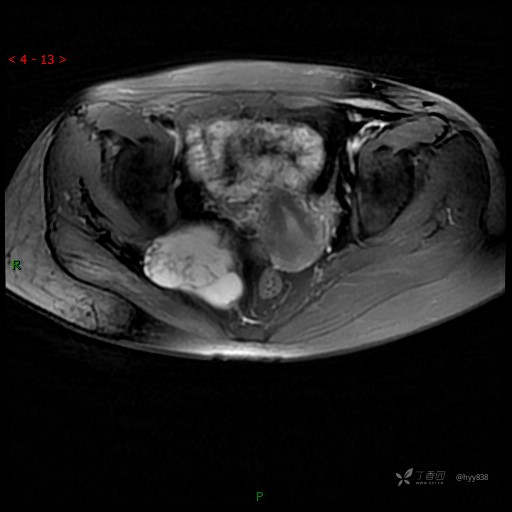

T2WI cor